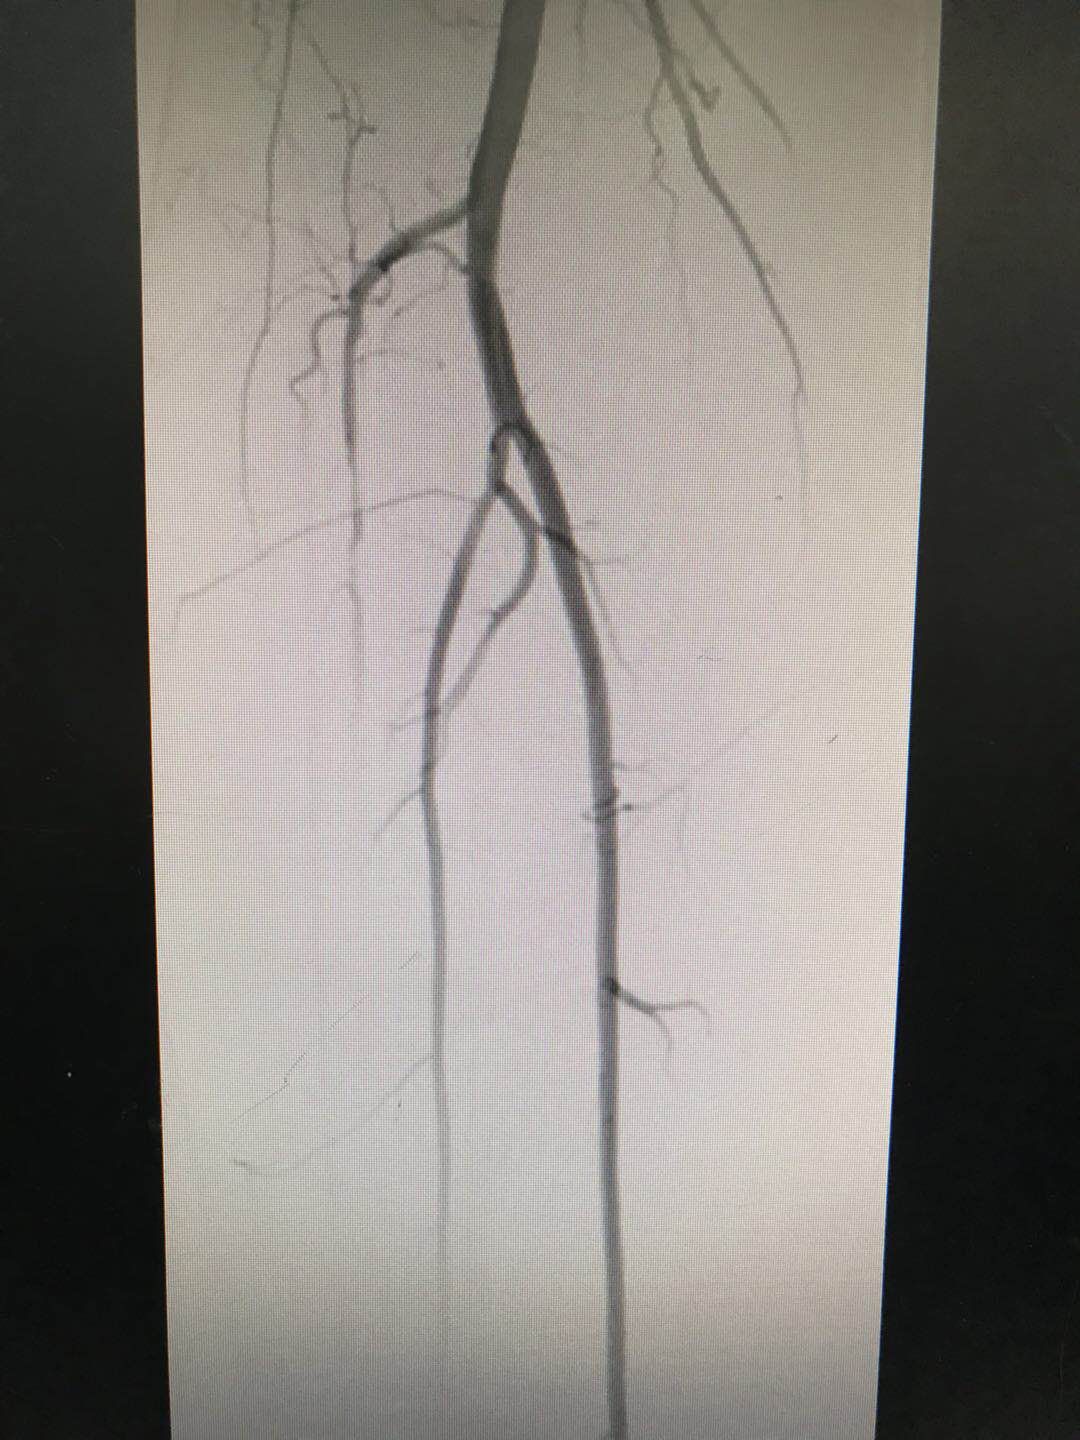

2018-08-02西安市第九医院内分泌科完成首例下肢动脉造影术

7月24日上午,西安市第九医院内分泌科马磊主治医师与介入科钟勇进主治医师合作,完成内分泌科首例糖尿病下肢动脉硬化闭塞症患者下肢动脉造影术。术中显示该患者右侧胫前... -